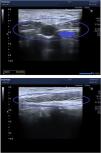

Ante la sospecha de persistencia de uraco infectado, se realizó una ecografía abdominal, en la que se objetivó un trayecto, con una cavidad rellena de líquido, que comunicaba el ombligo con la vejiga (fig. 2). Se administró amoxicilina-ácido clavulánico durante 15 días, con mejoría de la lesión. En el exudado umbilical se aisló Staphylococcus aureus; el urocultivo fue estéril. Se derivó a cirugía para su exéresis.

A: Ecografía abdominal: Nódulo subcutáneo hipoecogénico de 18 mm de diámetro. Abdominal ultrasound: Hypoechogenic subcutaneous 18 mm-diameter nodule. B: Ecografía abdominal: Trayecto hipoecogénico que comunica el ombligo con la vejiga. Abdominal ultrasound: Hypoechogenic tract that connects the umbilicus to the bladder.